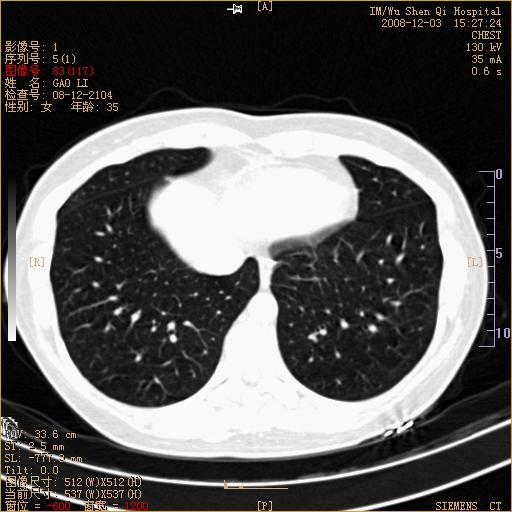

标题: CT16895:女,35岁,反复咳嗽数月,只传部分图像,是否考虑 [打印本页]

标题: CT16895:女,35岁,反复咳嗽数月,只传部分图像,是否考虑

左下肺支扩

典型“印戒征”。

印戒征,支持支扩.

左下肺扩支

印戒征,支扩